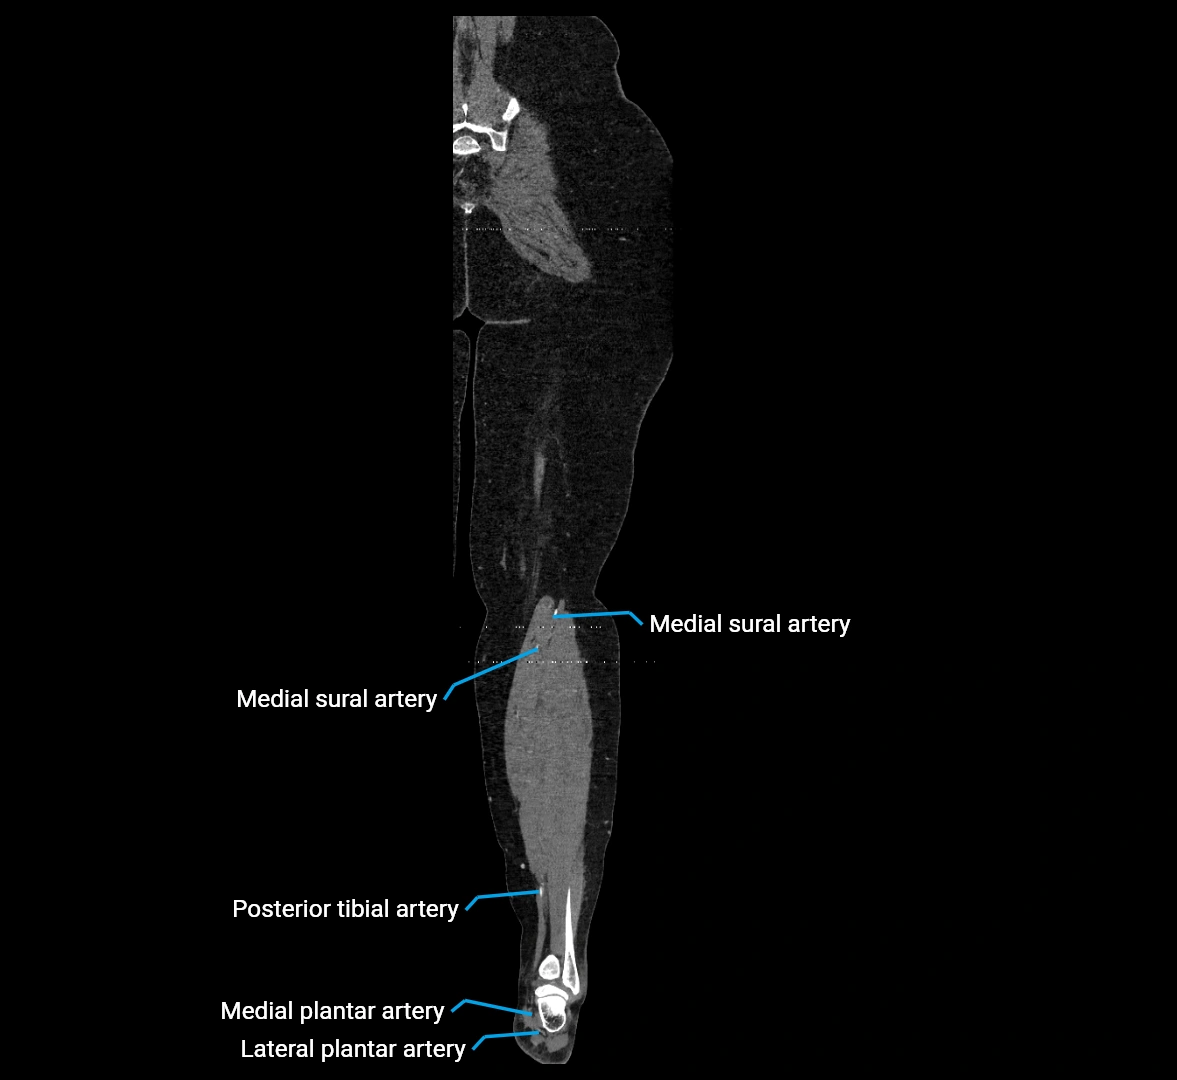

CT images

image

Contrast-enhanced CT (CTA):

• Gold standard for abdominal aortic imaging

• Provides excellent detail of lumen, wall, aneurysm, thrombus, and branch vessels

• Multiplanar and 3D reconstructions help in aneurysm measurement, stent graft planning, and dissection evaluation